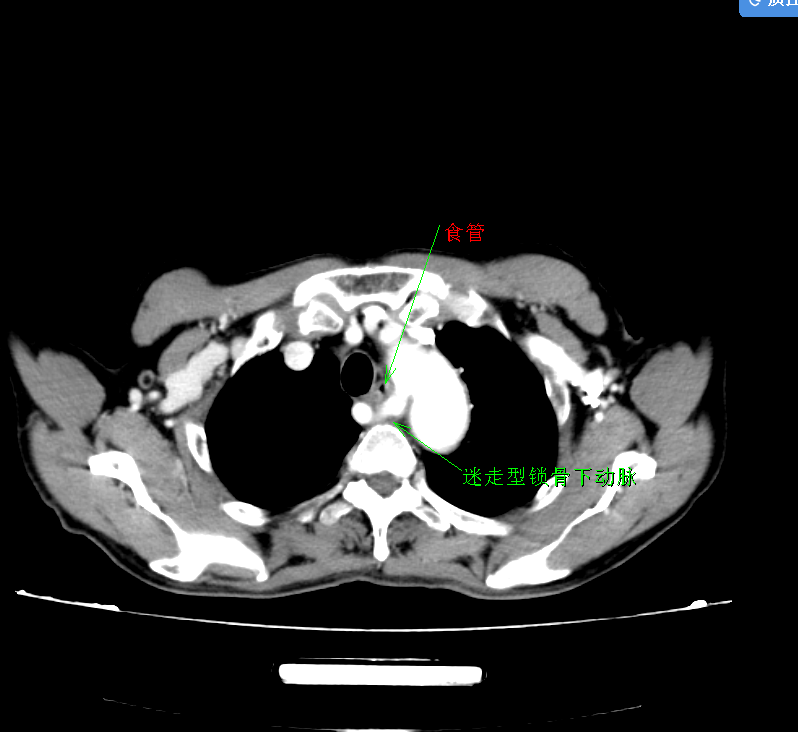

患者高先生(化名)因进行性吞咽困难前来就诊,原本以为只是普通的肠胃问题,却在检查后被确诊为食管中上段鳞癌。更棘手的是,进一步的影像学评估发现,他竟合并先天性迷走性锁骨下动脉——这一发病率不足 1% 的血管畸形!

正常情况下,右锁骨下动脉应从主动脉弓正常分出,而高先生的右锁骨下动脉却异位至食管后方,形成“血管环”,紧紧包裹食管及气管。肿瘤与变异血管如同纠缠的藤蔓,不仅让传统手术入路充满风险,稍有不慎,血管误伤就可能引发致命性大出血,甚至导致脑部供血障碍,手术难度堪称“地狱级别”!

术前CT